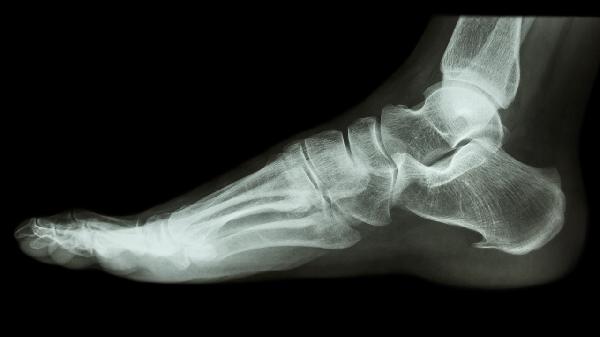

脚跟骨刺的治疗方法包括物理治疗、药物治疗和手术治疗,往里面打针并非首选方案。脚跟骨刺可能与长期负重、足部结构异常、慢性炎症等因素有关,通常表现为足跟疼痛、行走困难等症状。

足跟骨刺可通过生活方式调整、物理治疗、药物治疗、手术治疗等方式缓解,具体方案需根据病情严重程度选择。 1、生活方...

脚上长骨刺可能由长期劳损、体重过重、关节退行性变、痛风性关节炎等原因引起,通常表现为局部疼痛、活动受限等症状。 ...